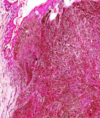

Liver cirrhosis Loss of the normal lobular architecture which is replaced by regeneration nodules surrounded by fibrous septae. Central veins are absent.The fibrous septae show chronic inflammatory cellular infiltrate Red: regeneration nodules black: fibrous septa

43

Diagnosis Describe Behavior

Hepatocellular carcinoma Section in liver which has malignant tumor formed of infiltrating trabeculae and sheets of malignant hepatocytes separated by CT. The tumor cells are polygonal Malignant